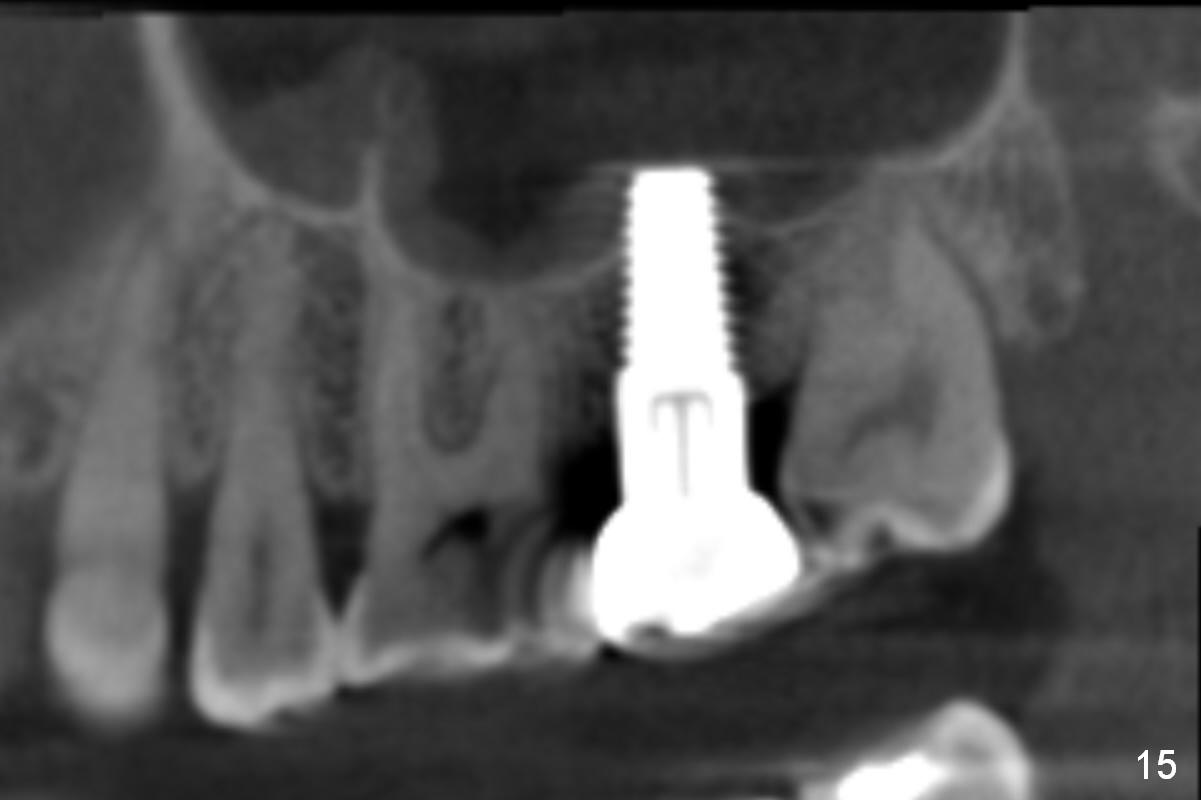

CBCT taken 23 months post cementation shows no abnormality (Fig.15-17). On the contralateral side, the apex of the tooth #15 is immediately inferior to the sinus floor (Fig.18 (sagittal section), 19 (coronal section)). The immediate implant seems to be unavoidably entering the sinus. The implant seems to be normal 3 year 5 months post cementation.